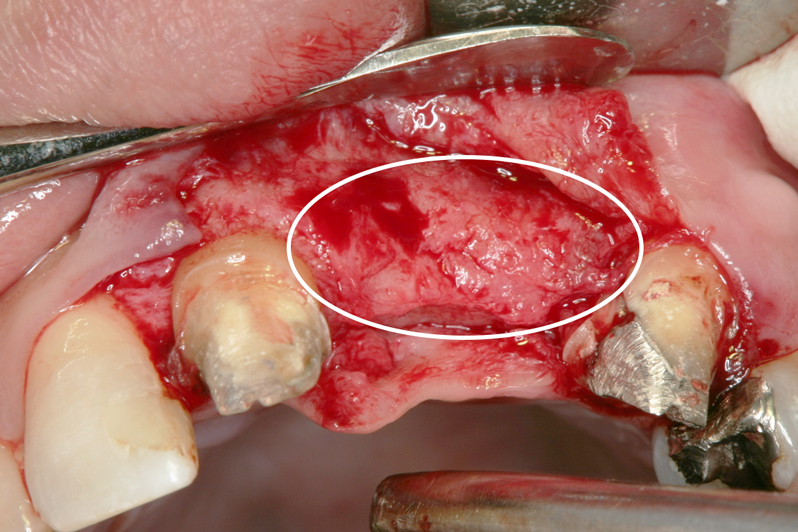

【ソケットシールドテクニックにて頬側骨の形態を維持する (右の様な骨のへこみを作らない)】

【通常の抜歯により唇側骨(外側の骨)が吸収してへこんだ症例】

※ 通常、ソケットシールドテクニックは前歯部領域に用いるが小臼歯部でも採用しました